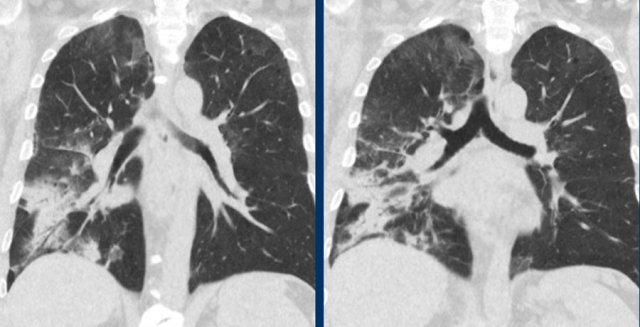

Viral pneumonias show overlapping features on CT.

Influenza virus infection can result in bilateral ground-glass opacities, consolidations and crazy paving that appear similar to COVID-19.

Typical features of influenza are:

- Mucoid airway impaction

- Linear opacities

- Central distribution (as shown in these two cases)

In addition, vessel thickening and upper lobe involvement seem to occur more frequently in the abnormal COVID-19 parenchyma than in other viral pneumonias.